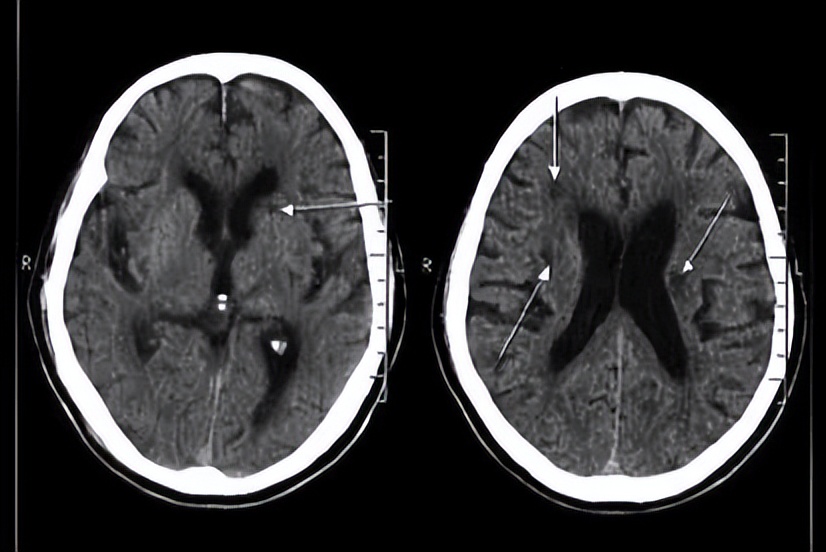

给脑部供血的动脉血管堵塞引起的神经细胞因为缺血缺氧而造成的坏死就叫小 脑梗死 。大动脉血管闭塞引起的较大体积的脑组织坏死,症状往往较重。而腔隙性脑梗死呢,往往是大的动脉血管分出的单个的小穿支动脉血管,这个直径呢大概在 0.2到0.8毫米 ,这一类血管闭塞所引起的,这一类梗死的体积和范围往往比较小,脑梗死 病灶直径 往往在 0.2到15毫米 之间。由于脑组织很软,缺血坏死以后啊,往往会出现液化性坏死,因此呢,在脑梗死的后期,脑组织液化以后就会 留下个小洞 ,这个洞就是所谓的 腔隙 。 也就是说腔隙性脑梗死是小动脉血管闭塞引起的 。

最常见的原因就是 高血压、高血脂、高血糖 等问题,其次呢,与 低密度脂蛋白 胆固醇的升高,与 吸烟、酗酒 都有关系。另外呢,少部分人还可能与基因遗传有关系。有人说腔梗不引起症状,这种说法是错误的。尽管腔梗的病灶体积小,如果影响到脑部的重要结构,比如说基底节的内囊区,或者是脑干等等重要的位置,完全可以引起单个肢体或者是偏侧肢体的瘫痪,或者是麻木等感觉异常,还可以引起语言的障碍。另外呢,腔梗往往不是单发的,三高等问题,它不可能只破坏脑部的一根小血管,也就是说 腔隙性脑梗死往往都不是一处 ,而多发性的腔梗甚至会 引起痴呆,步态异常,大小便障碍 等多种问题。

但是很多人会说,我体检中发现了腔梗,平时并没有赵大夫所说的那些症状,这就是是腔梗的一个特点,也是很多人说腔梗无害论这个健康误区的来源。去年在我国的一项 研究中表明 ,腔梗患者中有 超过30%的人是没有明显症状的 ,但是这类人在未来的 5至10年中 ,腔梗的 复发率极大 。因此,腔隙性脑梗死就是脑梗死的一种,无论是从发病机制还是病理基础来说,它确实都属于脑梗死。只是呢,这类疾病在早期的症状相对轻微,甚至近一半的人可能没有明显的症状。